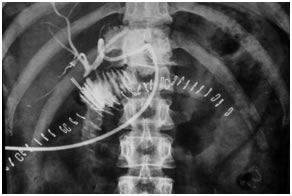

Post operative PTBD gram showing a patent high hepaticojejunostomy